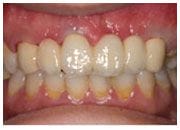

植牙過程

治療後